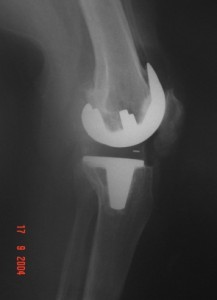

Radyoloji; Ayakta basarak çekilen grafiler, gerekirse MRI görüntüleriniz, kemik yapınız ve yumuşak dokularınız hakkında bilgi verecektir.

Ameliyatta kıkırdağın ve kemiğin hasarlı kısımları çıkartılacak, bacaktaki deformasyon düzeltilecek, yumuşak doku ve ligamentler dengelenecek, çıkartılmış olan kemik yüzeylere kemik çimentosu yardımı ile metal ve polietilen (plastik ara yüzey) implantlar yerleştirilecektir. Daha sonra yumuşak dokular ve cilt dikilecek, eklemde biriken sıvı ve kanı boşaltmak için konulan dren bir gün sonra çıkartılacaktır.